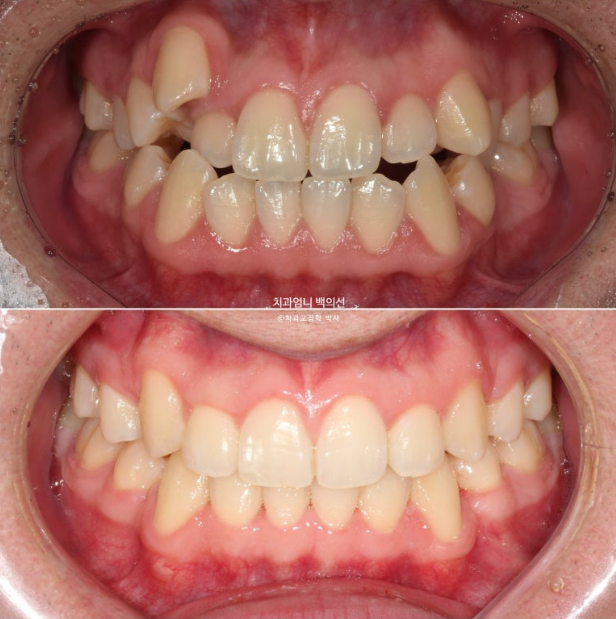

이제 전 후 비교 보겠습니다.

22.09~25.04

재제작은 총 2회 하였으며 치료기간은 2년 6개월 입니다. 중간중간 장치제작기간을 제외하면 실제 치료기간은 2년 2개월 입니다.